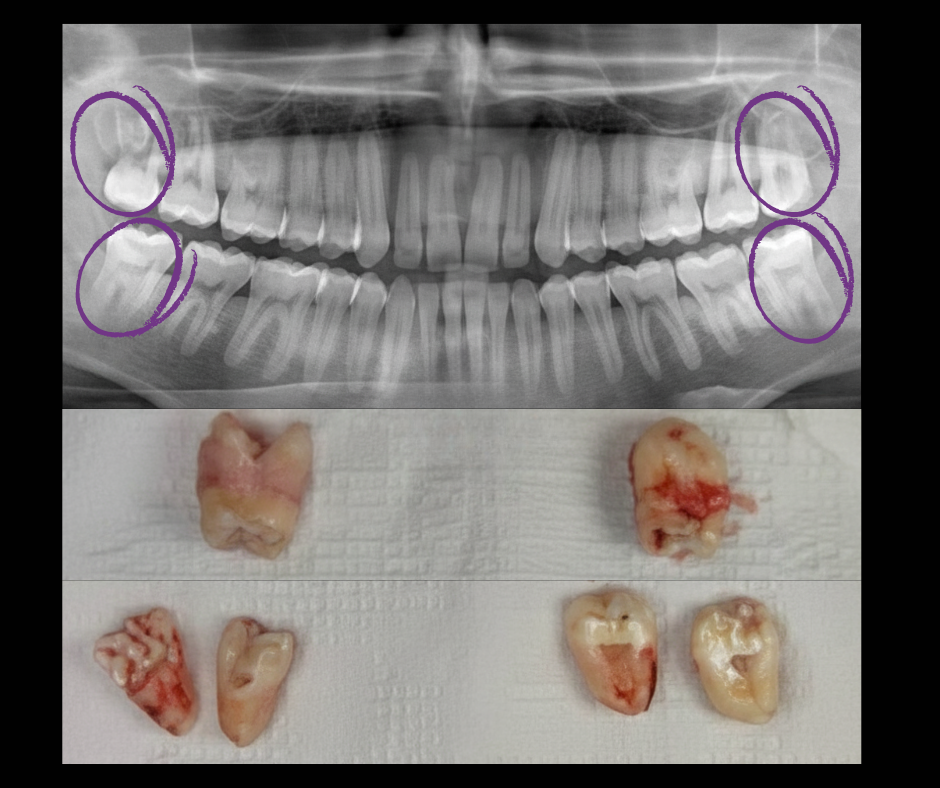

TERCEROS MOLARES (MUELAS DEL JUICIO)

Las muelas del juicio, también conocidas como terceros molares, son las últimas piezas dentales en aparecer. Suelen erupcionar entre los 17 y 25 años, y en muchos casos no tienen el espacio suficiente para salir correctamente, lo que puede causar molestias o problemas más serios.

Los terceros molares pueden quedarse retenidos o mal posicionados, provocando:

Inflamación o dolor en la zona posterior de la boca

Infecciones recurrentes

Desgaste o daño al diente de al lado

Desplazamiento de los demás dientes

Quistes o lesiones alrededor de la muela

Por estas razones, es fundamental realizar una evaluación radiográfica y un diagnóstico oportuno.

¿Cuándo se recomienda extraerlos?

Tu odontólogo puede sugerir la extracción cuando:

No hay espacio suficiente para su erupción

Están generando dolor o infecciones

Están presionando otros dientes

Presentan caries o fracturas difíciles de tratar

Se requiere prevenir futuras complicaciones (como parte de un plan de ortodoncia)

¿Cómo es el procedimiento?

La extracción de terceros molares es un procedimiento seguro, realizado bajo anestesia local y en algunos casos sedación. Con una adecuada técnica quirúrgica, las molestias posteriores son mínimas y recuperarte suele ser rápido.

Experiencia en casos de terceros molares complejos